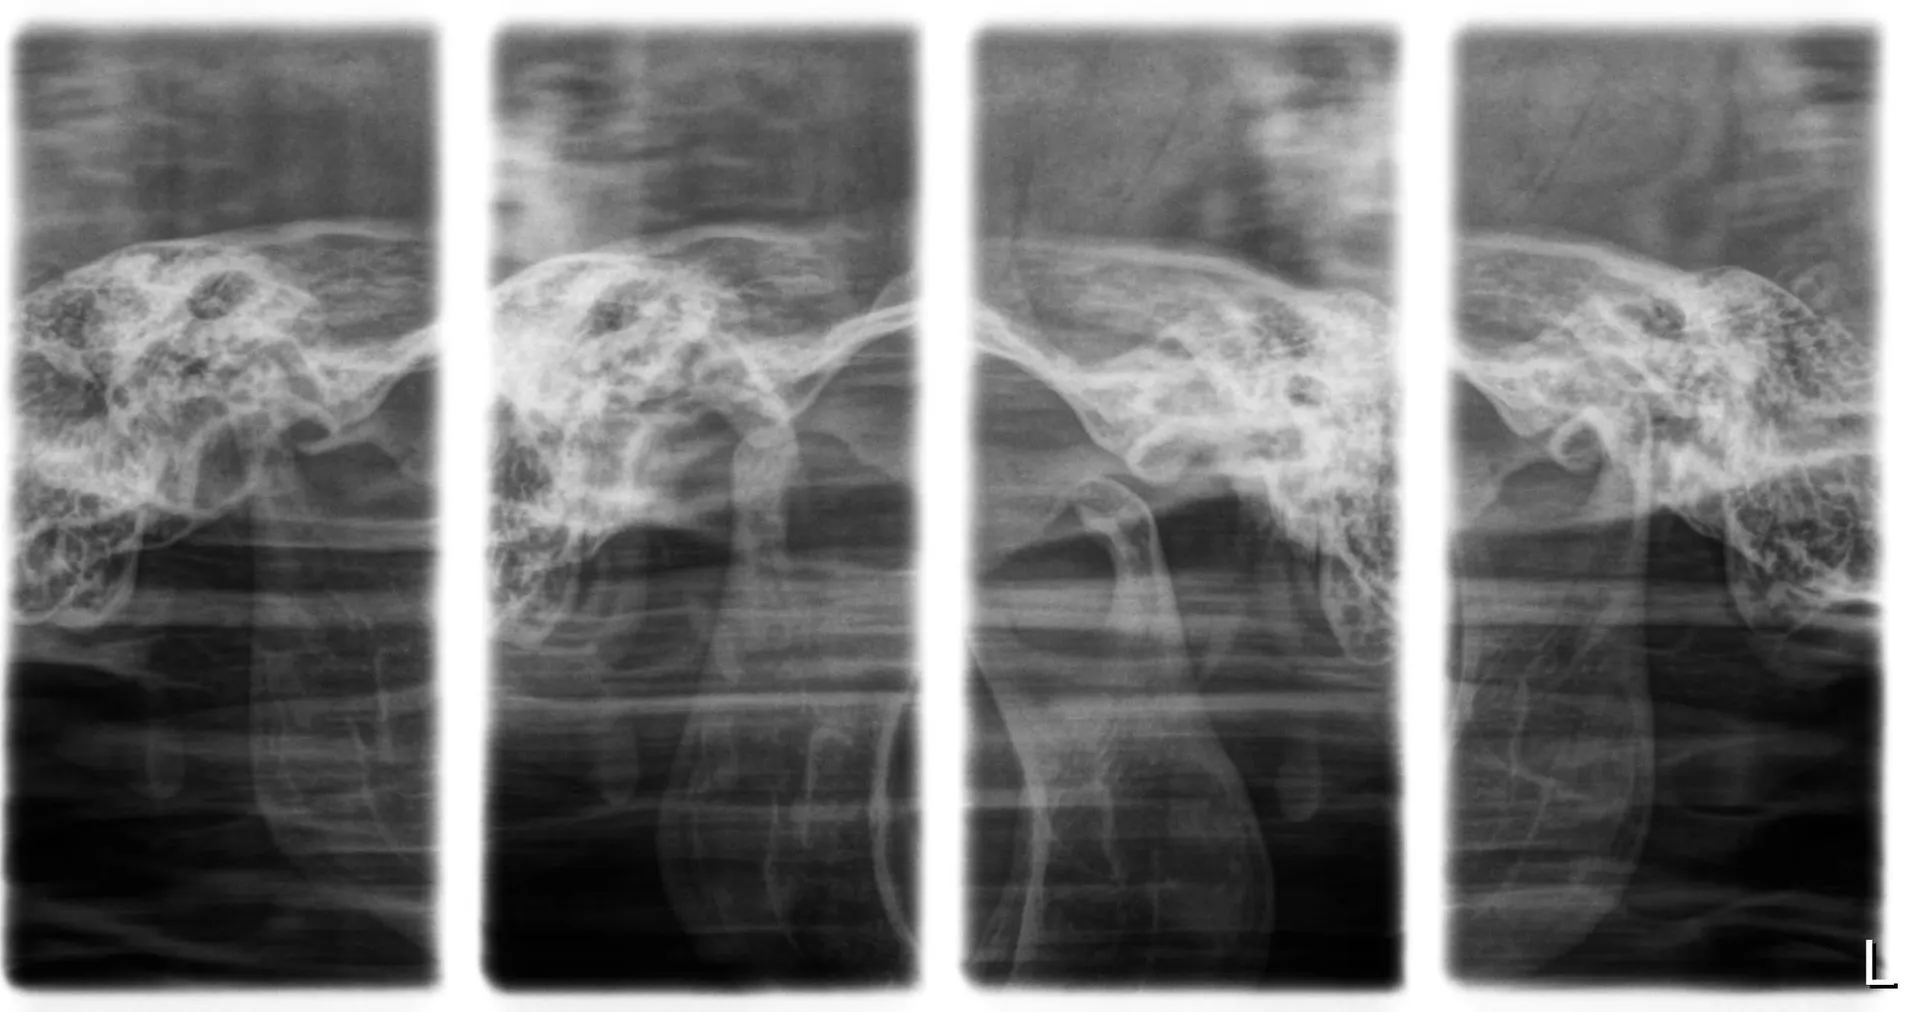

RX ATM (Escanografía)

Es una técnica radiográfica convencional, previa a la tomografía computarizada, que permite obtener imágenes parciales y selectivas de la ATM mediante movimientos lineales del tubo de rayos X y del receptor, con el objetivo de disminuir la superposición de estructuras vecinas.